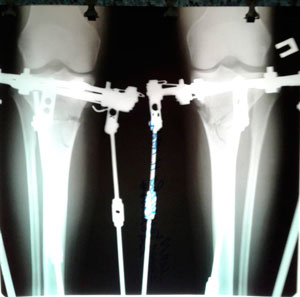

Дата операции - 04.07.2019г.

Дата снятия аппаратов - 10.10.2019г.

Срок сращения - 95 дней.